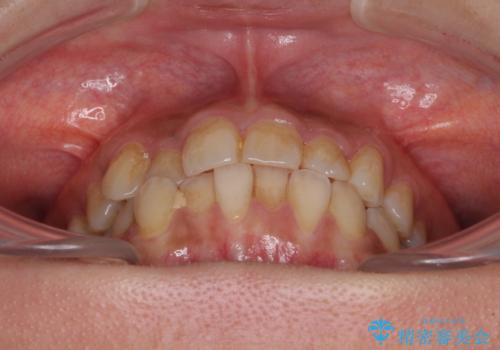

前歯のデコボコとクロスバイト インビザラインによる矯正治療

- 上下のクロスバイトと前歯のデコボコを気にして来院された患者様です。

インビザラインを用い、IPR(歯と歯の間を削る)と歯列全体を拡大させることで、歯並びを整えていくこととしました。

懸念されたとおり、右下のクラウン部分が全く咬み合わず、仕上げの段階で治療期間が長くなりました。